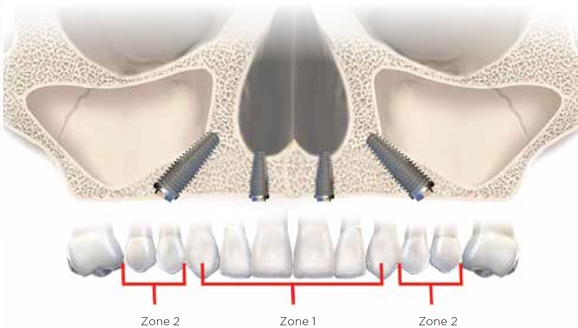

Radiographic evaluation of the edentulous maxilla is necessary for determining whether axial, tilted, or zygomatic implants would be indicated to establish optimal posterior support with proper anterior-posterior distribution of implants for a fixed prosthesis. Because the edentulous maxilla is divided into three radiographic zones, a systematic assessment of the residual alveolar bone available for implant placement can be made. In this pretreatment screening protocol, the alveolar bone supporting the maxillary anterior teeth is designated as zone 1, while the premolar region is considered zone 2 and the molar region zone 3 (Figure 4). Analysis of the radiographic results according to this scheme can enable the surgical and restorative team to devise a preliminary treatment plan. In complex situations, 3-dimensional (3D) radiographic evaluation may still be necessary to confirm the preliminary conclusions.

Fig 4. The zones of the maxilla.

Figure 4